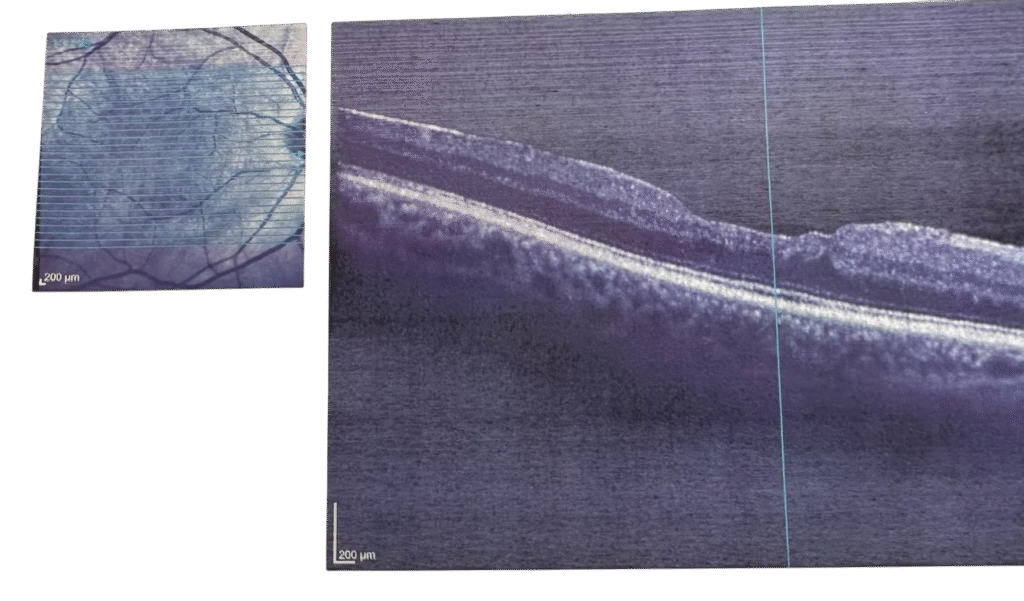

Resim 2: Makula deliği sonrası

Tanı

Gözün ‘MR’ ı veya ‘TOMOGRAFİSİ’ olarak da düşünülebilecek bu işlem , saniyeler içinde makula tabakalarının mikron düzeyinde kesinti alınır. Deliği çapı, evresi ve yapısı OCT ile net bir şekilde belirlenir

Kendiliğinden kapanma ihtimali çok küçük olan ( Evre 1 hariç) bir hastalıktır. Tedavisi cerrahidir. Erken safhada yapılırsa görme geri kazanımı daha yüksektir.

Pars Plana Vitrektomi (PPV) Ameliyatı